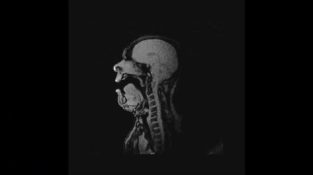

Laulaja MK

MRI-skannaus suoritettiin keskiviikkona 4. toukokuuta Freiburg Institute of Medical Medicine -instituutissa Saksassa, esittää oopperalaulaja Michael Volle suorittamaan kappale ooppera saksalaisen säveltäjän Tannhäuser [...]